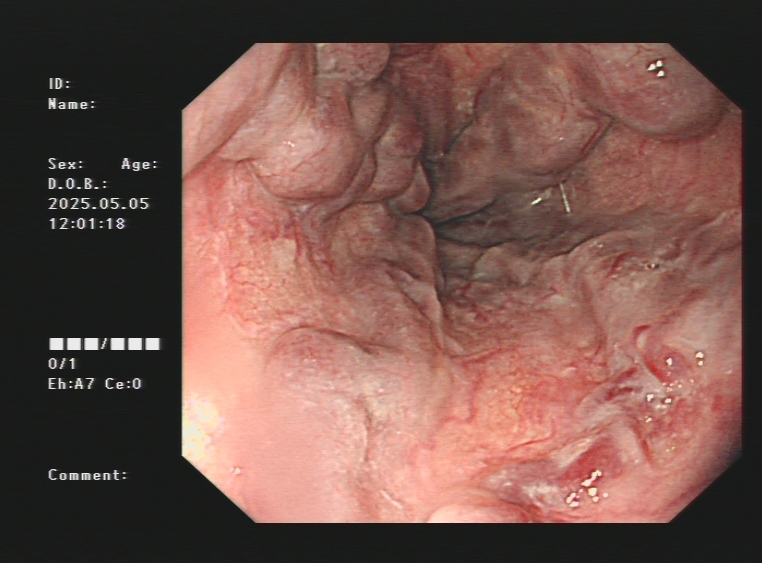

1.上消化道出血常见原因:消化性溃疡(胃溃疡、十二指肠溃疡)、食管炎、急性糜烂出血性胃炎、上消化道肿瘤(食管癌、胃癌)、剧烈呕吐造成的食管贲门黏膜撕裂伤、肝硬化引起的食管胃底静脉曲张。以下是一些常见的上消化道出血内镜图片:

肝硬化引起的食管及胃底重度静脉曲张镜下止血